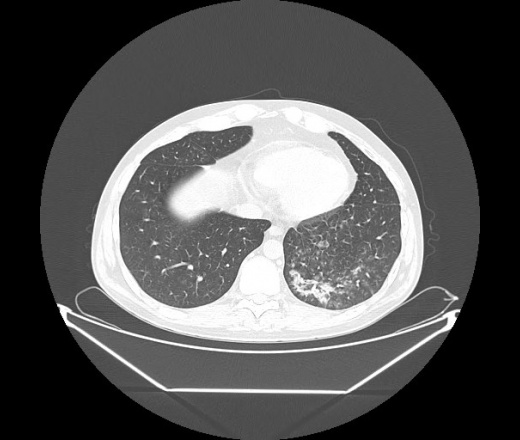

М. 1984 г.р.  Лихорадка 39, кашель , одышка.. и надоевший всем вопрос- "типично ли для ковид?" ( в настоящее время на него обязательно нужно дать ответ в своем протоколе)

На мой взгляд нетипично для ковид: много центрально-расположенных поражений, лобарное поражение нижней доли слева. 50/50

Не типичая картина для ковид.

КТ-признаки двусторонней бактериальной пневмонии.

Все верно, здесь абсолютно нетипичная картина, несмотря на матовое стекло с ретикулярными изменениями, но почему-то  посчитали иначе. Кстати,  "малыша" не заметили)?

Добавил 6 день

Что за малыш? Будущий абсцесс? Не заметил. Только о туберкулёзе подумал

+ 1?  Зона очень похожа была на формирующийся абсцесс, даже по рентгенпризнакам. Еще хотела спросить, но постеснялась. А на контроле видно

да, это я о абсцессе.